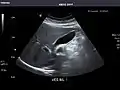

Pancreas

Pancreas: Visualized portions unremarkable.